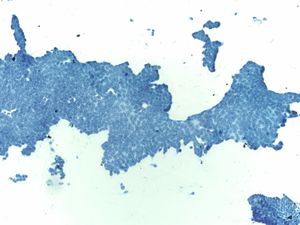

Duodenal Epithelium– MN05-N08394

- Flat and cohesive monolayered sheet with a honeycomb pattern; occasionally papillary groups (intact villi), smaller groups and single cells

- Non-mucinous glandular cells with brush border

- Sporadically placed goblet cells appearing as “fried eggs” with a sheet

- Lymphocytes (“sesame seeds”) in the epithelium